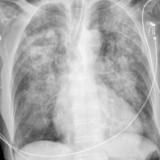

Heart failure

Album: Heart failure

Date: 11/05/2005

Size: 24 items

Views: 56821